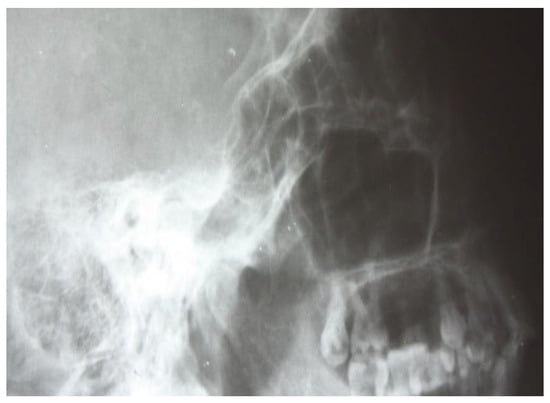

3.1.1. Conventional Radiology

3.1.2. Computed Tomography and Magnetic Resonance Imaging